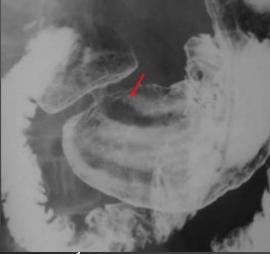

Image radiologique TOGD de

helicobacter pylorie . |

Image

chronique |